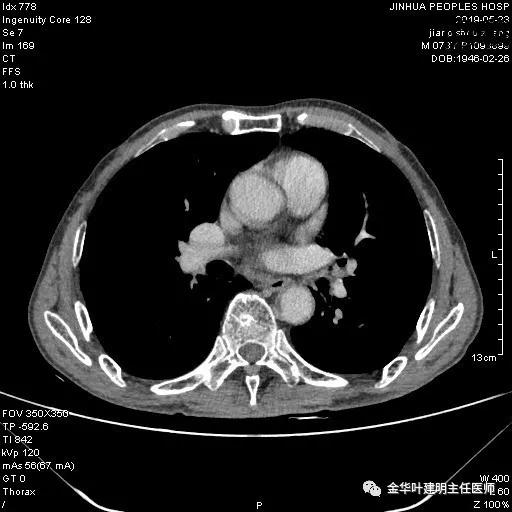

患者,男性,73岁,金华人。因“咳嗽咳痰伴胸闷2月,检查确诊左肺癌1周”入院。气管镜: 气管支气管内较多脓性分泌物,左肺上叶前段管腔新生物,局部活检、毛刷。气管镜病理:(左肺活检)鳞癌。阅胸部CT见左上叶开口处新生物,考虑需左上叶袖式切除及淋巴结清扫。具体CT表现如下:

术前检查冠脉CT示:左冠前降支近段多发钙化斑块伴管腔重度狭窄(约85%),建议DSA检查。但追问病史以往平时无胸痛或胸闷症状,运动试验提示可疑阳性(上斜型压低),活动后胸闷气闭症状不明显,既往否认高血压、糖尿病。所以经过心内科会诊讨论,认为还是可以进行手术。术前冠状动脉CT示: